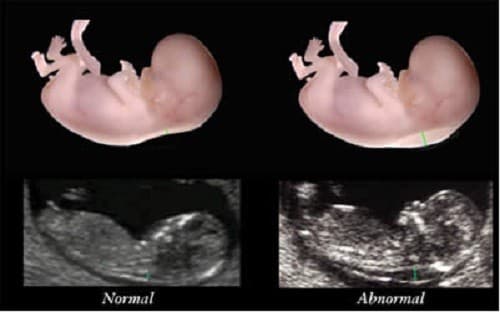

Độ dày da gáy hay còn gọi khoảng sáng sau gáy là sự kết tụ chất dịch dưới da ở vùng gáy. Tất cả thai nhi ở tuổi thai từ 11 tuần đến 13 tuần 6 ngày thì đều có chất dịch này kết tụ ở vùng gáy, tuy nhiên, với thai nhi mắc hội chứng Down số lượng chất dịch này tăng lên đáng kể làm cho độ mờ da gáy tăng lên, dày hơn. Việc đo độ mờ da gáy là cách để sớm phát hiện hội chứng Down.

Độ mờ da gáy cho biết thai nhi bình thường, khi kết quả đo độ mờ da gáy khi thai nhi được 11 tuần tuổi khoảng 2mm, 13 tuần là 2,8mm. Nếu đo độ mờ da gáy lớn hơn 3mm, thì có thể bé có nguy cơ mắc hội chứng Down khá cao. Kết quả này có thể phán đoán chính xác nguy cơ trẻ mắc bệnh Down.

Tuy nhiên có khoảng 1/20 – 1/25 thai phụ đo độ mờ da gáy bị kết luận “nguy cơ cao” nhưng vẫn sinh con khỏe mạnh. Nếu thấy trường hợp thai nhi có nguy cơ bị bệnh Down cao, bác sĩ sẽ chỉ định thực hiện thêm một số xét nghiệm khác để có kết quả chính xác.